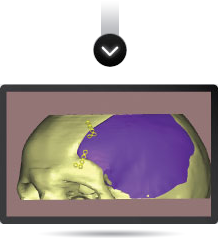

La reconstrucción utiliza como información de entrada imágenes obtenidas por técnicas de diagnóstico (TAC o MRI). A través de un software especializado se procesan las imágenes y se logra modelar en tres dimensiones cualquier región anatómica con patologías diversas.

En el modelado 3D digital se pueden incluir implantes ortopédicos como placas, tornillos, mallas, prótesis, etc., y también modelados en 3D y en tamaño real en relación con el modelo anatómico. De esta forma es posible simular diferentes situaciones con las que el cirujano se enfrentará durante el proceso quirúrgico.

Una vez obtenida la información de la TAC o MRI y modelado el 3D digital, podemos modelar la prótesis que se necesita (por ejemplo, una porción de calota faltante) y posteriormente realizarla en resina plástica. De esta manera validamos la adaptación del futuro implante a la anatomía. El cirujano puede verificar las imágenes modeladas digitalmente o el prototipo en resina plástica, y sugerir modificaciones dando paso al proceso final.

Se aplica un programa informático validado para convertir y manipular la información de la TAC y crear un modelo de implante anatómicamente correcto.

Antes de la fabricación del implante, el cirujano puede elegir entre dos métodos de examen del implante PROTOLAB: 1) Un modelo del cráneo y del implante para ser examinado, marcado o aprobado;

2) Las imágenes informáticas del defecto, del implante y de éste acoplado en el defecto enviadas por medios electrónicos.